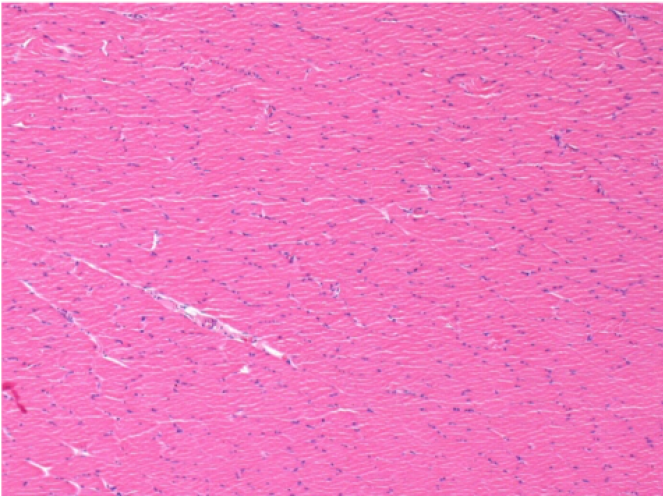

Л: Претибіальний м'яз - без лікування